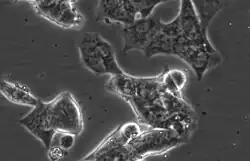

Representative phase-contrast image of LAPC4 cells. 32X magnification.

LAPC4 cells are a cell line of human prostate cancer commonly used in the field of oncology. The tissue was harvested from the lymph node metastasis of a male patient with hormone refractory prostate cancer which was then xenografted into SCID mice and later harvested and plated on tissue culture dishes, where it can be propagated as an immortalized prostate cancer cell line.[1][2][3]

LAPC4 are a lowly adherent, epithelial cell line with high Androgen receptor and Prostate specific antigen expression.[4] Unlike the other commonly utilized, Androgen receptor positive prostate cancer cell lines LNCaP and VCaP, LAPC4 have high expression of Keratin 5, a basal marker, as well as the luminal markers Keratin 8 and Keratin 18.[4] LAPC4 also expresses mutated P53 (R175H). [4]